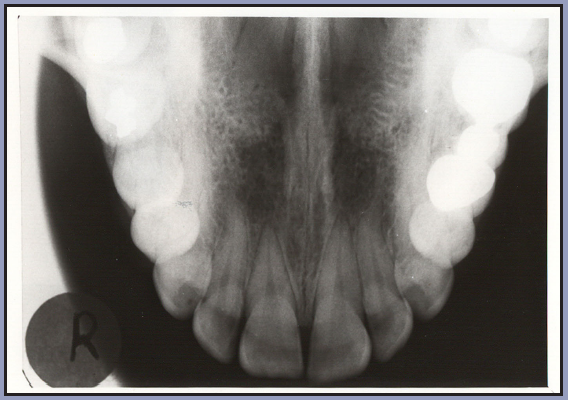

Uses:To view the anterior portion of the mandible for fractures, cysts, root tips, and periapical pathology. It provides a very good view of the symphysis region of the mandible as seen in Figure 66.

Patient positioning: The patient is seated with the head tilting slightly backward, so that the occlusal plane (ala-tragus line) is 45 degrees above the horizontal plane. Before any radiographs are exposed, the patient must be draped with a protective apron and thyroid collar. The apron must be properly placed to avoid interference with the radiographic exposure.

Receptor placement: Use a type 4 receptor. With the tube side of the receptor toward the mandible, the receptor is placed crosswise in the mouth, like a cracker. It is gently pushed backwards until it contacts the anterior border of the mandibular ramus. The patient bites down gently to maintain position.

Exposure factors: Follow the recommendations of the receptor and equipment manufacturer.

Direction of the central ray: The central ray is directed between the apices of the mandibular central incisors and the tube is angled at -55 degrees relative to the receptor plane, as in Figure 67.